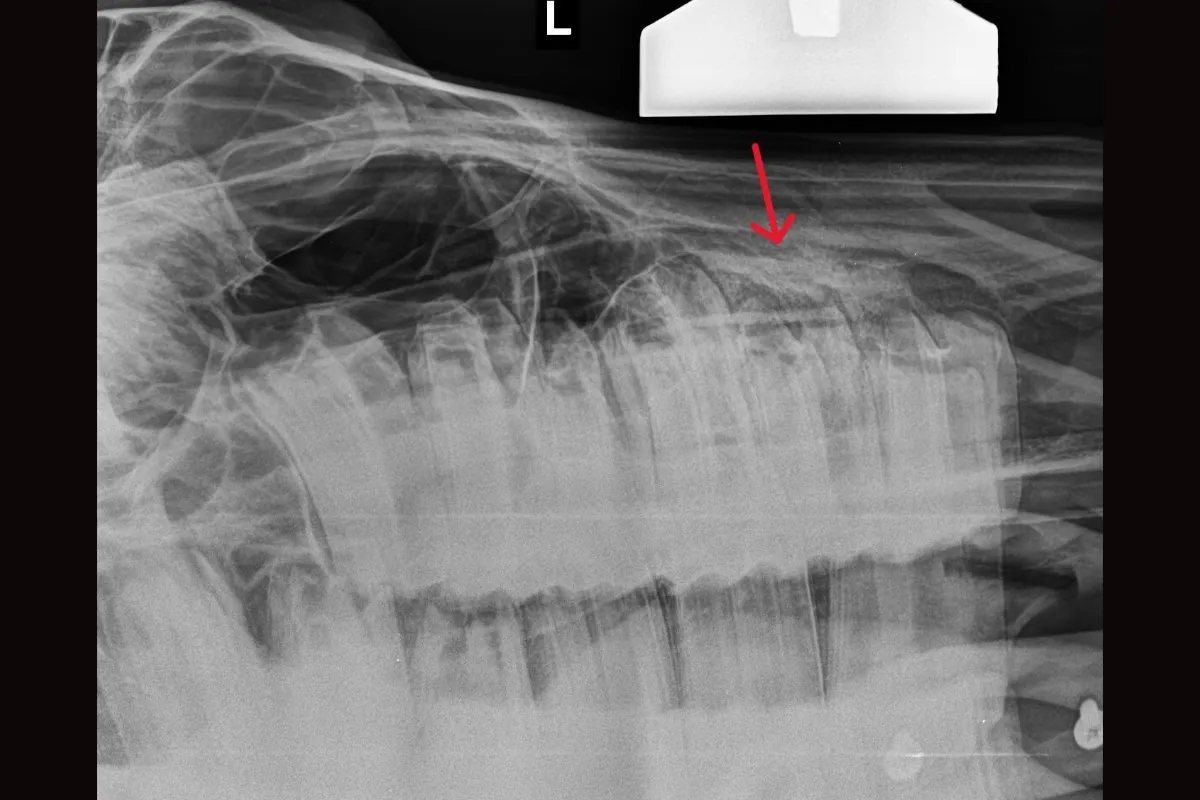

X-ray showing the affected tooth, with the arrow indicating the area of infection associated with the tooth root.